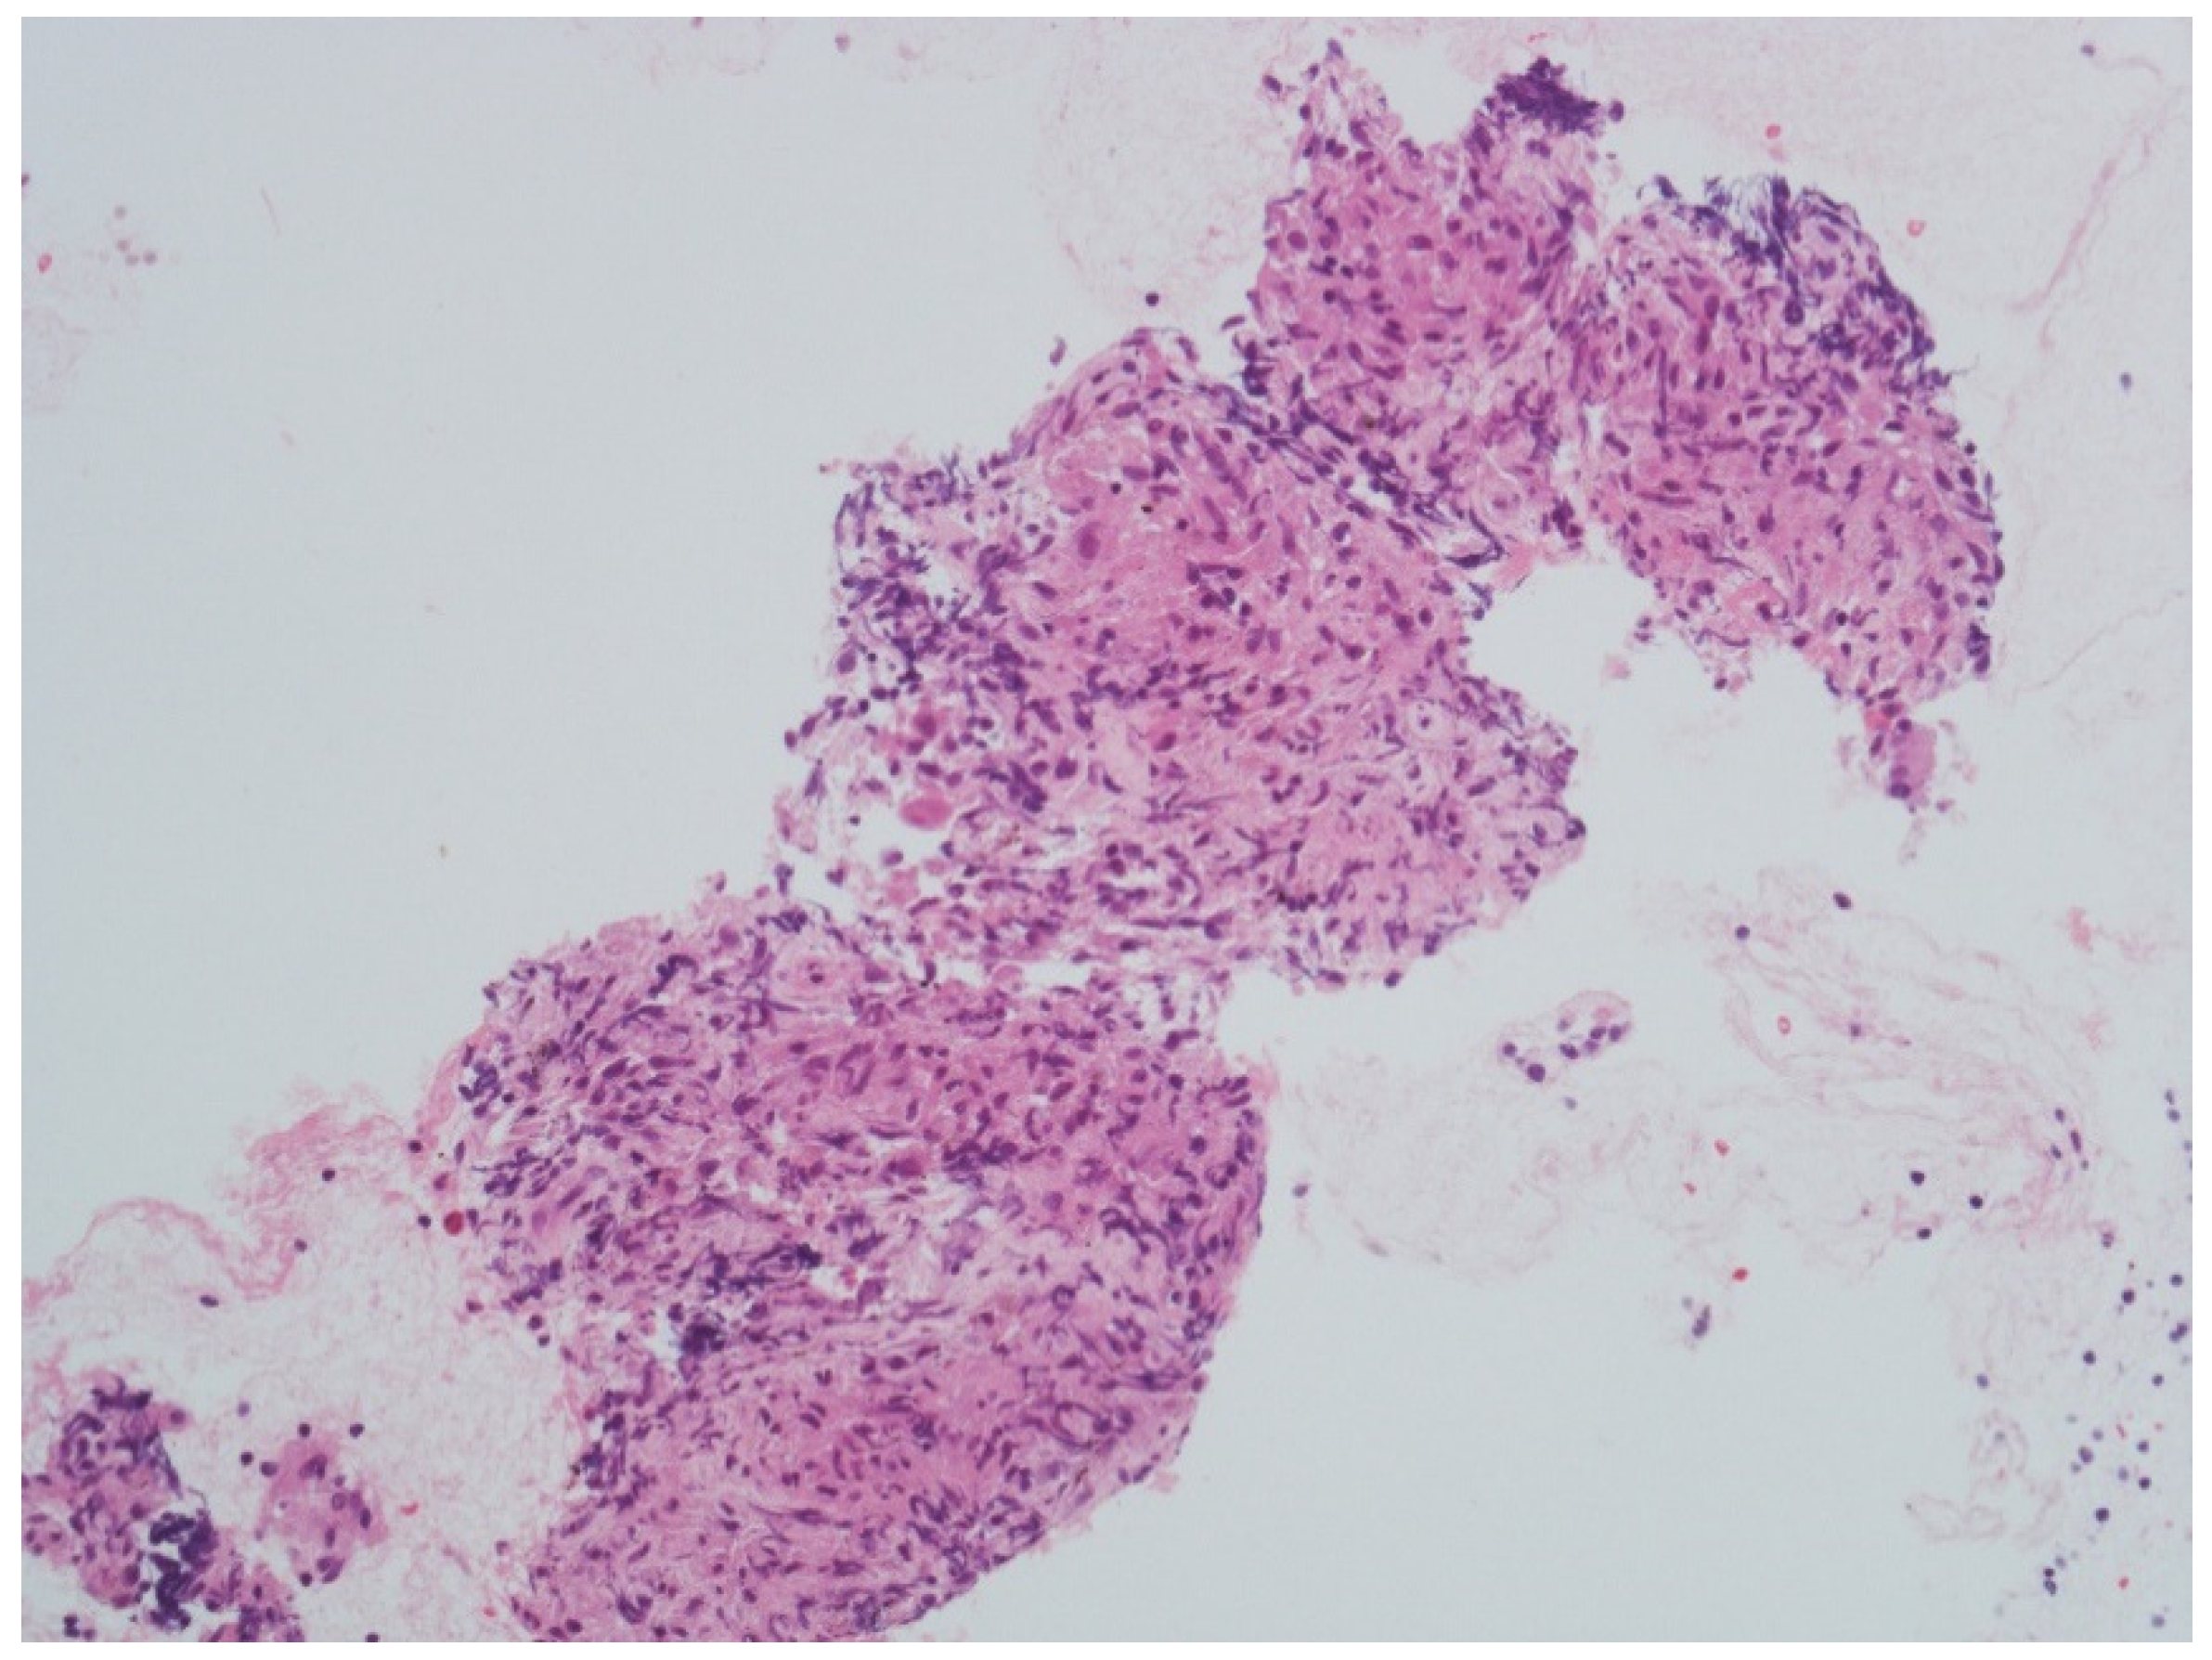

2. Case Report